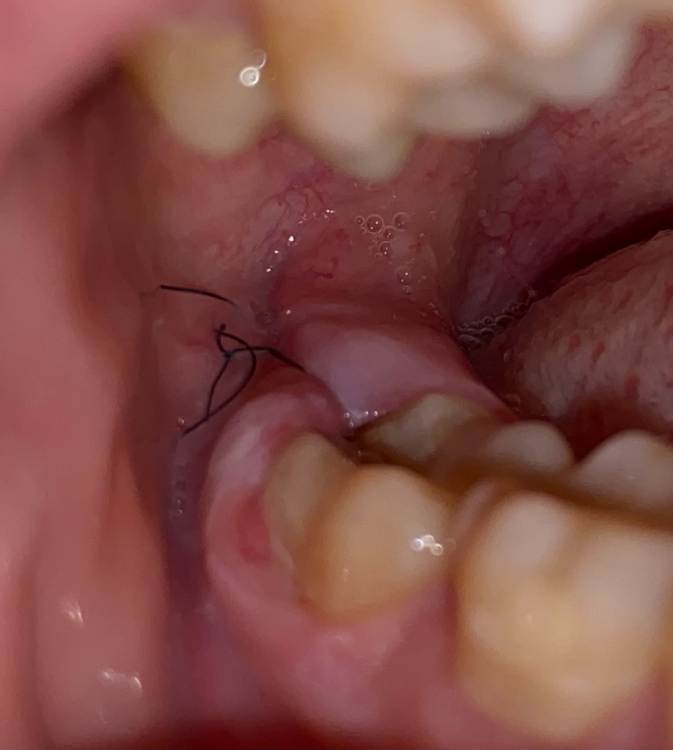

Karina21 Опубликовано 30 июля, 2021 Автор Поделиться Опубликовано 30 июля, 2021 (изменено) @Женька @Irouil Сегодня снова была у врача, промыли физраствором и наложили альвожил, попросили и дома перед сном промыть, записали на завтра на еще одну процедуру. Промывая приходится отодвигать десну начиная от середины 7 зуба не вредит ли это ему? Сказали что каждый день придется ездить на промывание, но я не понимаю как оно тогда заживать будет? Можно ли так часто промывать? Швы сегодня сняли не останется ли дырка если постояно промывать и отодвигать десну? Изменено 30 июля, 2021 пользователем Karina21 Ссылка на комментарий

Karina21 Опубликовано 30 июля, 2021 Автор Поделиться Опубликовано 30 июля, 2021 @Irouil @Karina21 полоскать сказали и дома физраствором вдоль этих линий. Десна легко отодвигается в местах, которые отметила красным маркером начиная от середины 7 зуба. Сегодня промыли и положили альвожил, сейчас не болит вообще, но я не понимаю процесс заживления, если постоянно промывать, десна разве не будет просто болтаться потом? Ведь рану раскрывать почти как книгу(чтобы промыть) приходится вот типа как над восьмым зубом сверху капюшон из десны бывает и десна не герметично над зубом находится Ссылка на комментарий